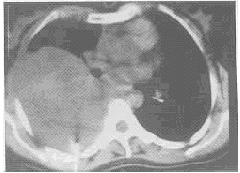

CT检查: 右后纵隔巨大软组织密度肿块,向右胸腔凸入,大小约15.0cm×13.5cm,密度欠均匀,其内可见少量点状钙化影,肿块广基底与后侧胸壁相连,邻近骨质未见明显异常改变,气管、支气管通畅,右主支气管、中上叶支气管向前方移位,纵隔内未见肿大淋巴结,右胸腔少量积液(附图)。俯卧位CT引导下胸穿活检细胞学检查显示细胞有明显异型性。提示:后纵隔恶性肿瘤。

手术所见: 肿瘤位于右上后纵隔,与肺、胸膜、背部肋骨有浸润、粘连,大小20cm×15cm×14cm,形态不规则,无包膜,肉眼观呈鱼肉状,内有出血、坏死区,右胸腔积液100ml。病理诊断: 后纵隔血管肉瘤。